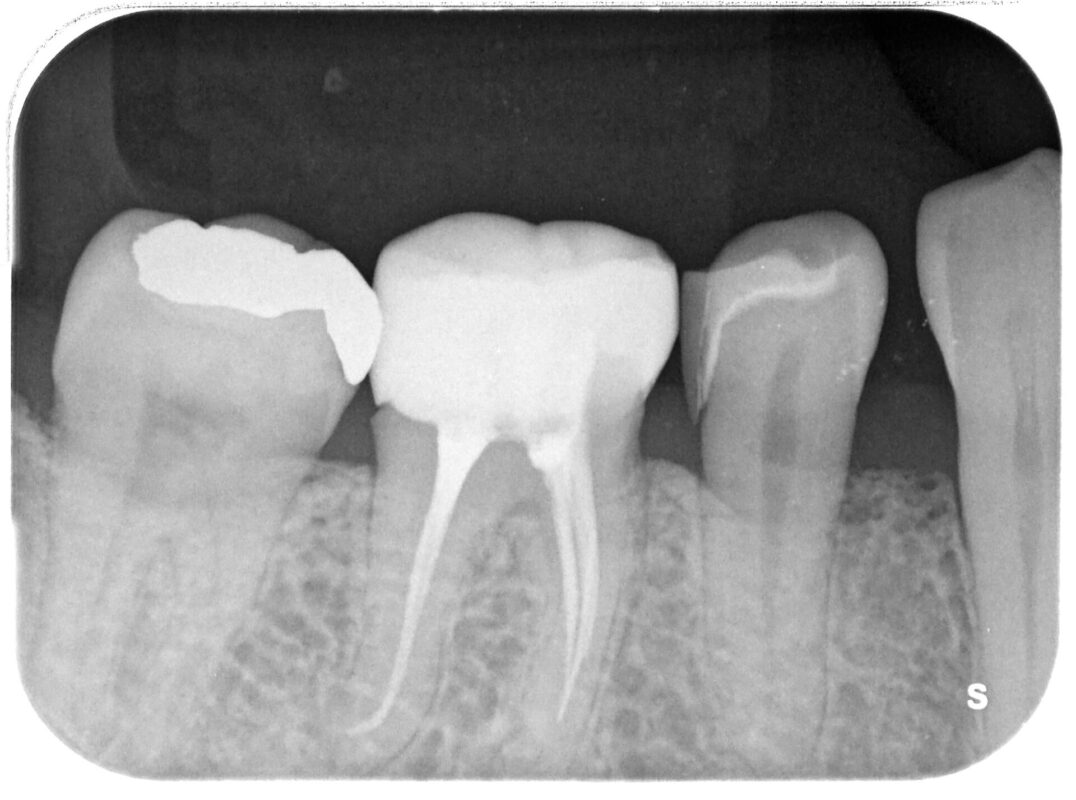

術前

症状はほとんどないのですが、他院で行われた比較的最近処置したセラミッククラウンの境目に段がで

きており、内部に穴が空き、黒く変色しているとのご相談。

レントゲン写真を撮ると、、、、、、

正直、最初は私も気が付かなかったのですが、根管治療に使用されるファイルが折れてそのままになっ

ていました。

レントゲン的には2本折れていると思ったのですが、実は3本折れて残留していました。